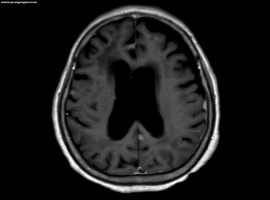

脑膜转移:隐秘而凶险的终极并发症

上厕所晕倒,很有可能是脑部有问题,如果没有加强核磁可见的病灶和异常,可以继续观察看是否还有其他神经系统症状,如步态不稳,失语,视觉和味觉改变等。如果逐步发现上述症状,要做好脑膜转移的准备。